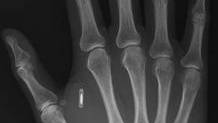

The person who does will find themselves inducted into the community of “grinders” – hobbyists who modify their own body with technological improvements. Just as you might find petrol heads poring over an engine, or hackers tinkering away at software code, grinders dream up ways to tweak their own bodies. One of the most popular upgrades is to implant a microchip under the skin, usually in the soft webbing between the thumb and forefinger.

This month at the Transhuman Visions conference in San Francisco, Graafstra set up an “implantation station” offering attendees the chance to be chipped at $50 a time. Using a large needle designed for microchipping pets, Graafstra injected a glass-coated RFID tag the size of a rice grain into each volunteer. By the end of the day Graafstra had created 15 new cyborgs.